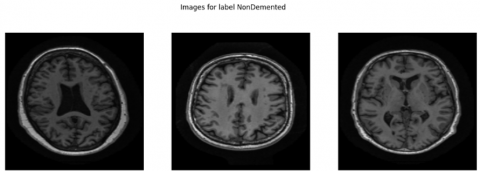

The structural parameters of this dataset show mild bias since it contains 1,216 NonDemented scans while MildDemented scans reach 1,792 images and VeryDemented scans total 706 images. The research data shows good clinical accuracy because healthcare professionals routinely examine more patients with MildDemented conditions. This visual representation in Figure 2 shows MRI cutting planes from each class to represent their structural and intensity differences. The anatomical differences between samples in cognitive processing centers become noticeable in these examples which supports accurate model functioning during training and inference. The varied content of this database enables deep learning models to become effective while they demonstrate multispectral capabilities for AD detection at an early stage.

Figure 2. Sample MRI images from different classes

A proper Exploratory Data Analysis (EDA) was performed in advance to uncover the structural features alongside visual elements and distribution imbalances throughout the dataset. The underlying database consists of 3,714 T1-weighted brain MRI images containing clinical labels of NonDemented, MildDemented and VeryDemented cognitive stage classifications. The three stages of AD organize into separate categories which the labels represent. The main goal of Exploratory Data Analysis included two objectives: first displaying representative images from each class category as shown in Figure 2 and second applying analysis techniques to examine statistical properties which would guide further preprocessing steps and model development.